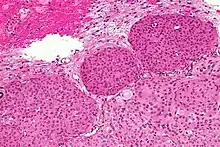

Histopathology of a typical WHO grade 1 meningioma, H&E stain. It is of the meningothelial histologic type, which is the most common meningioma type. It shows its typical findings:

- A woven architectural pattern

- Psammoma bodies (spheroid calcifications)

- Syncytial cells (having indistinct cell membranes) with eosinophilic (pink) cytoplasms

- Round uniform nuclei

- Whorls (concentric cell arrangements)[15]